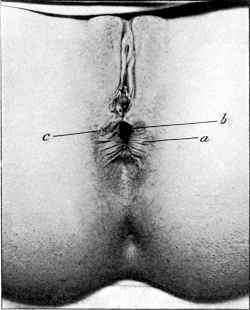

| 30. | Complete Laceration of the Perineum | 127 |

| 32. | Complete Laceration of the Perineum | 128 |

| 33. | Complete Laceration of the Perineum | 129 |

| 34. | Laceration of the Pelvic Floor | 132 |

| 35. | Repair of a Lacerated Perineum, with Non-union of the Sphincter Ani, before a Plastic Operation | 133 |

| 36. | Repair of a Laceration of the Perineum after a Plastic Operation | 133 |